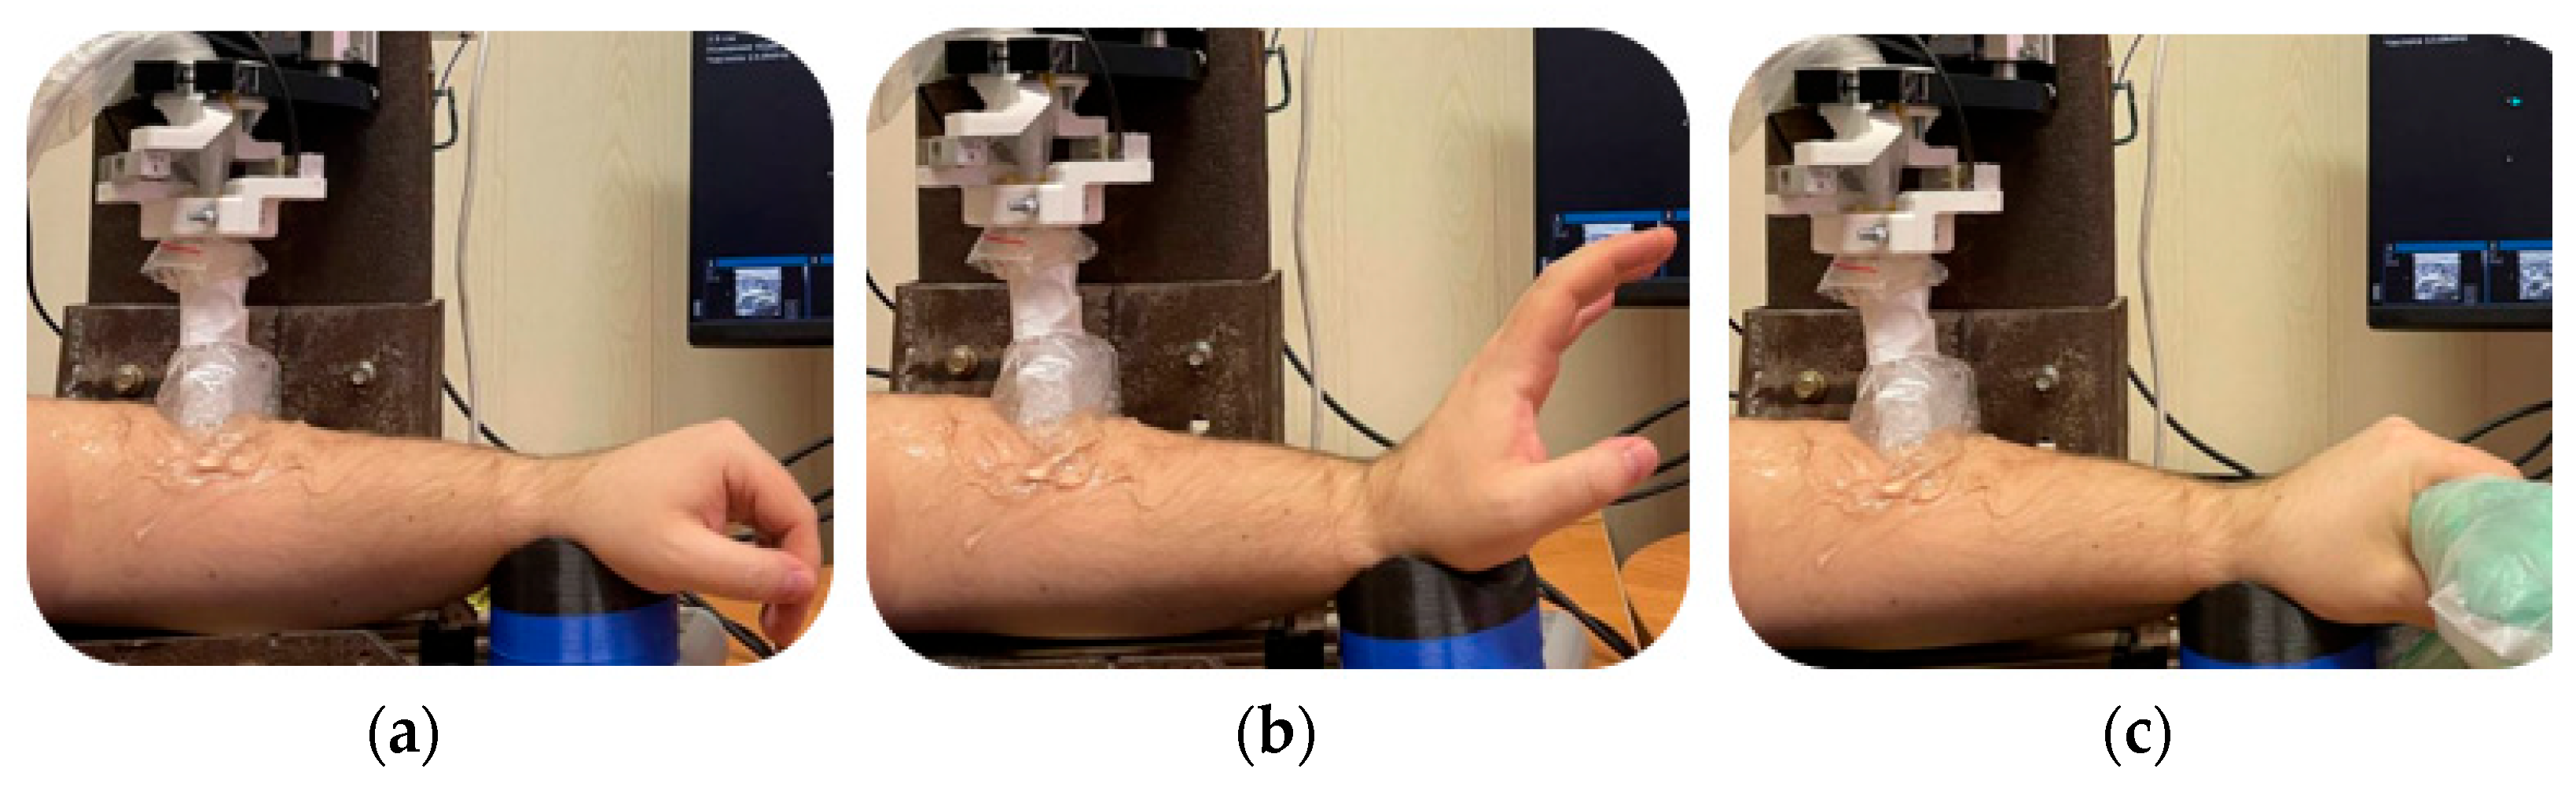

2.6. Measurement Design

3.2. Study of the Amplitude Parameters of the Electrical Impedance Myography Signal at Different Pressures of the Electrode System